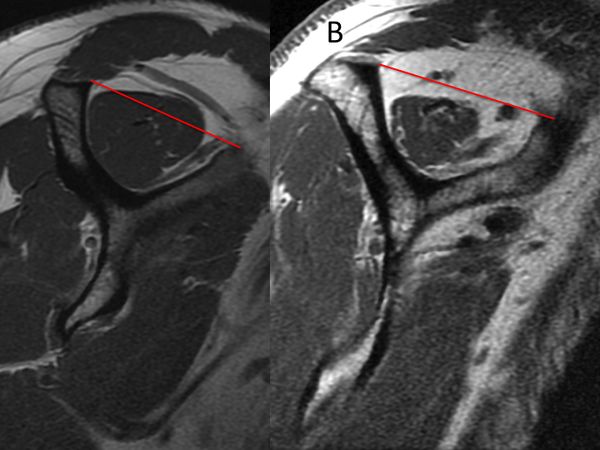

- The tangent sign is an indicator of advanced fatty infiltration and is a predictor of whether a rotator cuff tear will be reparable.